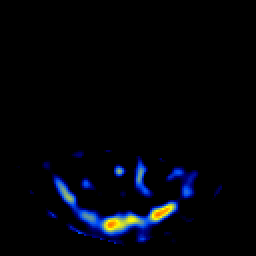

SPECT TL Study #8 -- Slice #12

[Home][Help][Clinical][Tour 1][Tour 2][Tour 3] Slice 12